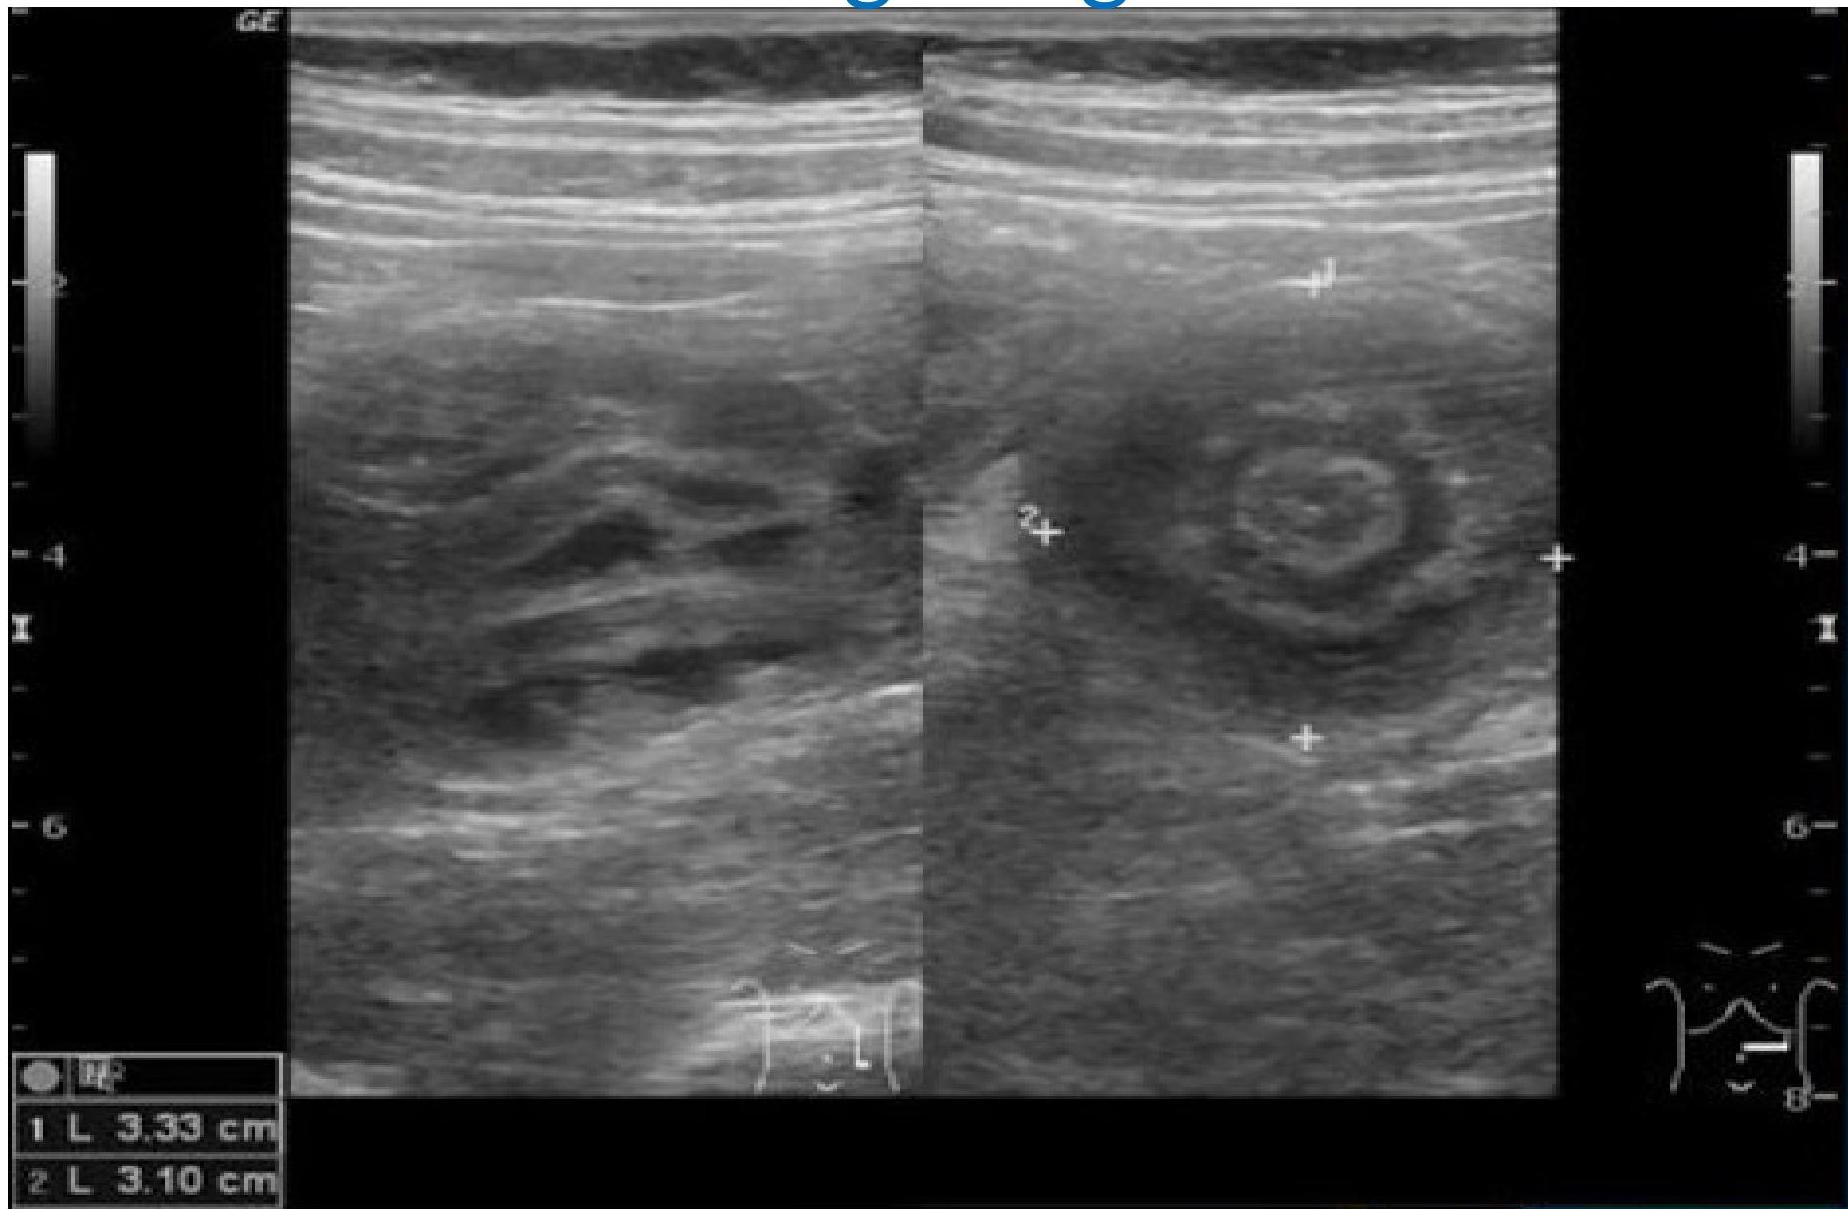

- Ultrasound is the method of choice and diagnostic â target sign.

Target sign

- Target sign : The invaginated portion of bowel appears as rings on a target on ultrasound.Â

Target sign in intussusception

Ultrasound abdomen (bowel; transverse plane)

Concentric alternating hyperechoic and hypoechoic rings are visible. The hyperechoic rings (green overlay) are formed by mucosa and the hypoechoic rings (red overlay) by submucosa. Together the alternating layers produce a target-like appearance (target sign; bullâs eye sign).